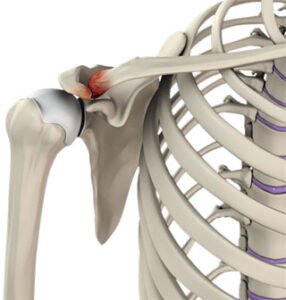

Illustrative depiction of Acromioclavicular joint arthritisThe AC joint is located at the junction of the acromion (a part of the shoulder blade) and the clavicle (collarbone). It is a synovial joint, enclosed by a capsule and supported by ligaments. The AC joint allows for overhead arm movement and is essential for the normal function of the shoulder.